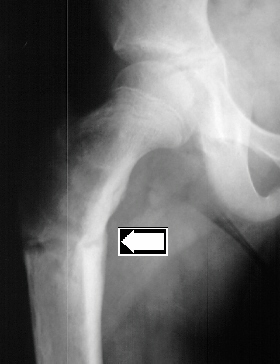

A 10 year old white female was evaluated in the orthopaedic clinic for leg length discrepancy. Her disease process has been characterized by early breast development at 3 years of age, menarche at the age of 6, and a pathologic subtrochanteric fracture after a trivial fall at age 8. She now complains of a limp and pain after long walks. The patient demonstrated a large pigmented lesion with irregular border located in the right upper back. There was a two centimeter leg length discrepancy by the block test.

The pain is probably from the expansion of the bone lesion in the femur.

This occurred outside playing when she slipped and sustained an acute fracture of the femur. There are no concerns about bringing her to the operating room without further work-up.

If this girl's pain continues with activity and gets worse over the next six months but the x-ray remains unchanged, curettage and bone grafting of the lesion is recommended.